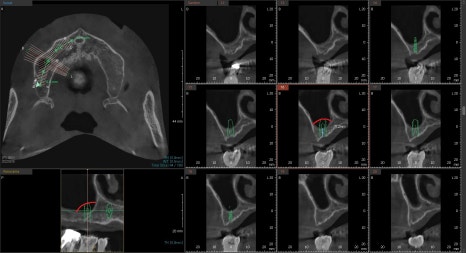

임시치아 상태 / 최종 엑스레이사진

하악 어금니의 경우 치조골 이식을 먼저 해놓은 후

보험 임플란트와 함께 단계적으로 수술을 했습니다.

수술 후 임시치아를 체결한 후

역시나 교합의 안정을 위해 2~3달 정도의

적응 기간을 거치고 있는 상태입니다.

오른쪽의 최종 보철물이 체결된 상태의 엑스레이 사진입니다.

앞니쪽의 뼈는 너무 종잇장처럼 얇아있기 때문에

최대한 골의 양이 허용되는 범위내에서 심고

작은어금니에서 지지를 같이 받는 구조로 설계를 하였습니다.